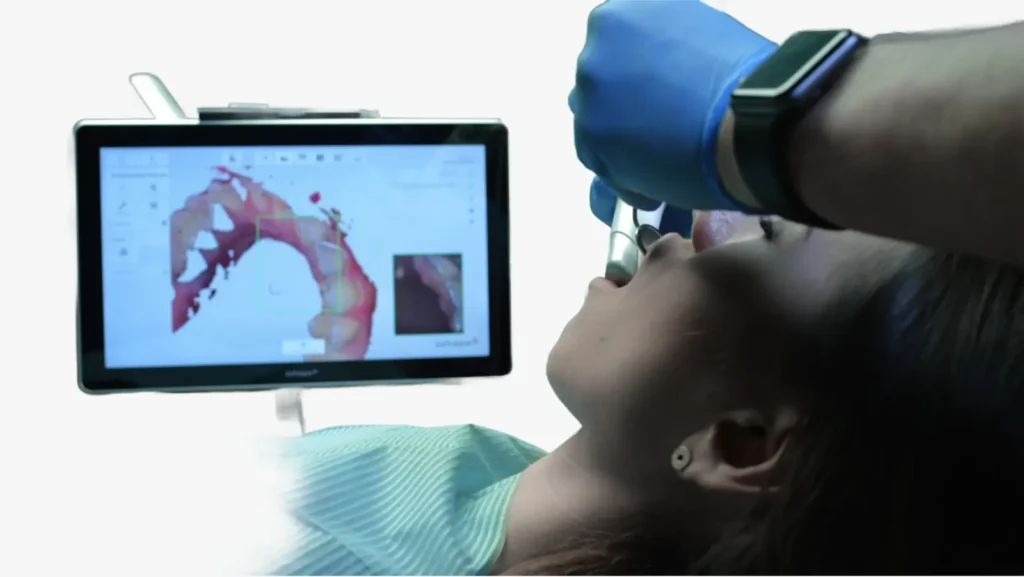

Servicio de escaneo dental a domicilio

Escaneo intraoral a domicilio

Llevamos la tecnología de escaneo intraoral directamente a tu consultorio o a tu clínica, ofreciendo una experiencia cómoda, rápida y sin impresiones tradicionales, brindando como ventaja en tiempo real guía de tallado